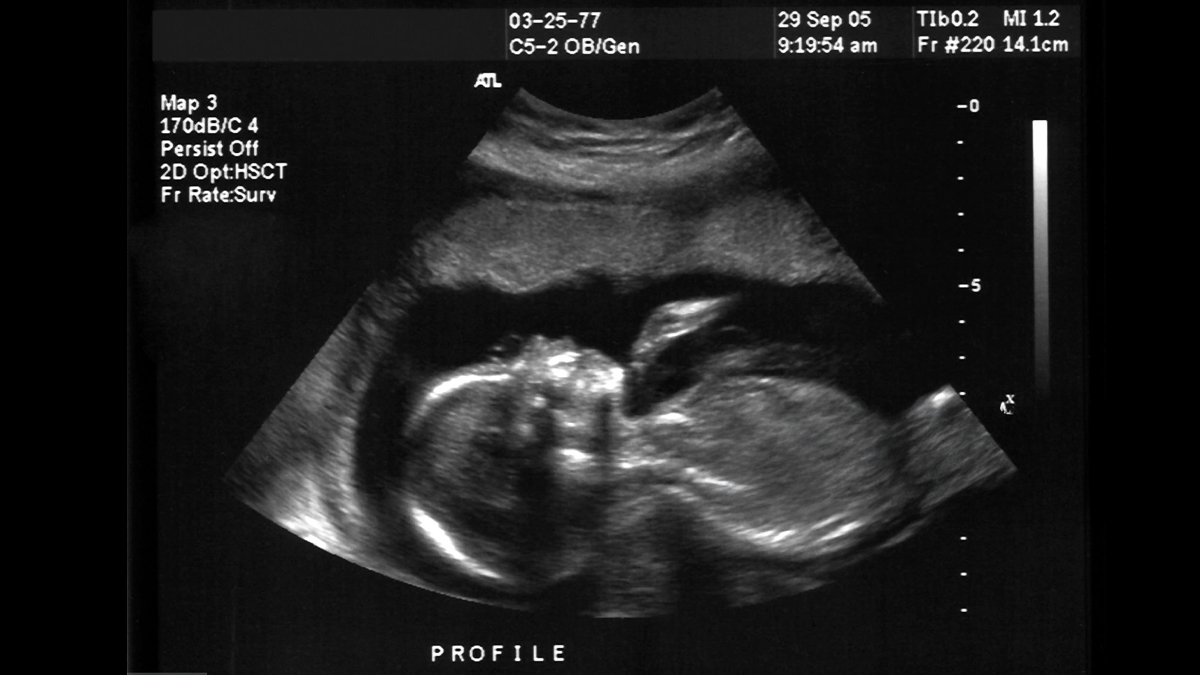

Pregnancy is a fulfilling transformation in a woman’s life, especially when everything goes well. However, it could be draining and uncertain as well, especially for the first time mothers. ‘Is the baby alright?’ ‘What if something is wrong?’ These are the sort of questions that could keep mothers-to-be up at night. Apart from regular check-ups though, there are several key signs that indicate everything is progressing well.

Dr Chetna Jain, Director Dept of Obstetrics & Gynecology, Cloudnine Group of Hospitals, Sector 14, Gurgaon, highlights five indicators of a healthy pregnancy:

Foetal movements are a reassuring sign that the foetal structures and functions are developing appropriately. The majority of mothers will start to feel movement (bear in mind this might be the flutters or kicks off a baby in between 18-25 weeks of pregnancy). As the pregnancy continues the movements become larger, and more regular. “A daily counting of fetal kicks during the third trimester is a great method for monitoring the baby's health. A healthy foetus will move a minimum of 10 times within two hours during periods of increased activity. An unexpected decrease or pattern change in movement should be brought to the attention of a physician at once,” Chetna says.